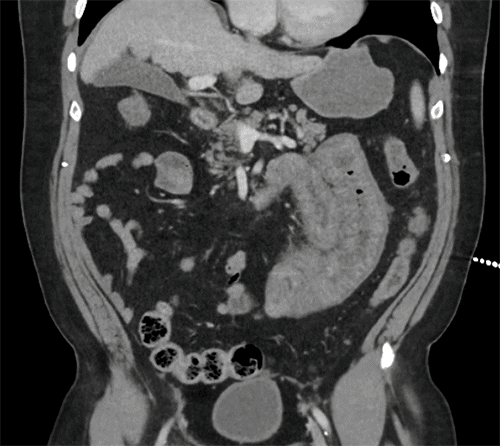

In the emergency department, a computed tomography (CT) scan of the abdomen and pelvis with intravenous contrast was obtained. The imaging revealed significant circumferential thickening of multiple small bowel loops with associated adjacent mesenteric edema and distal small bowel decompression. These findings were highly concerning for a closed-loop small bowel obstruction (Figure 2).

Figure 2. CT Findings of Small Bowel Vasculitis. Published with Permission

Contrast-enhanced CT scans of the abdomen. The images demonstrate diffuse, circumferential wall thickening of multiple small bowel loops accompanied by adjacent mesenteric edema and inflammatory stranding. Decompressed distal small bowel segments are also noted, features which, in this clinical context, were attributed to severe enteric vasculitis rather than mechanical obstruction